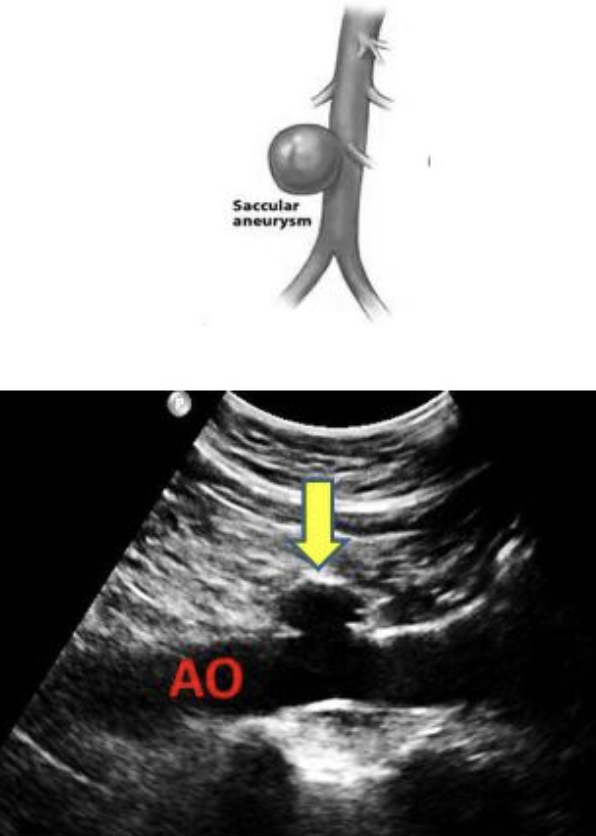

types of AAA

fusiform

saccular

fusiform aneurysm

circumferential enlargement of vessel with tapering at both ends

resembles a football

saccular aneurysm

localized dilation of vessel

spherical structure connected by a vascular mouth